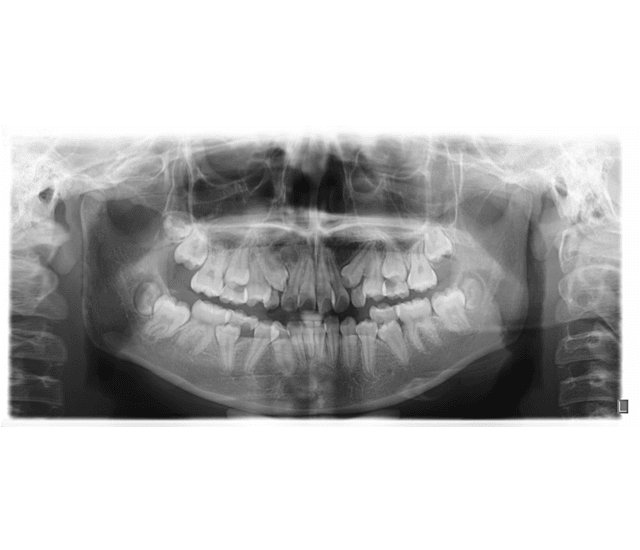

X-RAYS

Being Dentist clinics use the latest x-ray technology to diagnose oral health problems in a painless, non-invasive way. Though exposure to radiation can pose health risks, Being Dentist uses sophisticated, portable x-ray equipment that limits this exposure to negligible levels. Being Dentist clinics also use lead aprons and lead thyroid collars to protect doctors and patients from radiation. Finally, Being Dentist clinics adhere to the ALARA (As Low as Reasonably Achievable) principle, as defined by the U.S. Code of Federal Regulations 10 CFR 20.1003. The principle directs medical establishments to identify and use ways to minimize the exposure of medical personnel, patients and clinical staff to radiation.